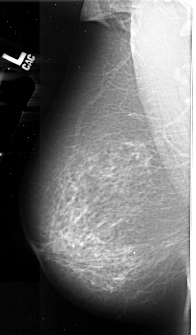

A_1009_1.LEFT_MLO

LEFT_MLO LINES 6016 PIXELS_PER_LINE 3526 BITS_PER_PIXEL 16 RESOLUTION 42 NON_OVERLAY